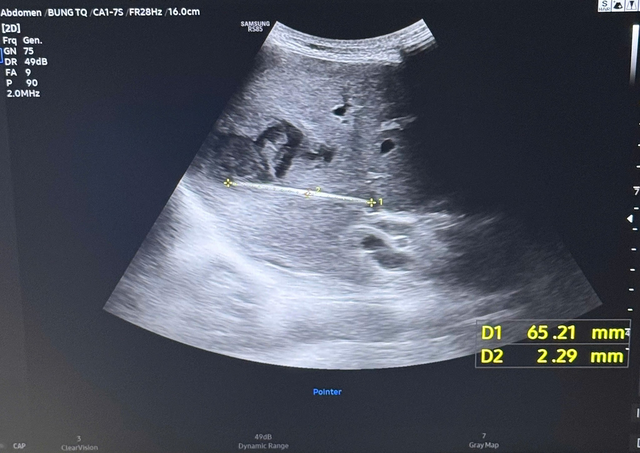

Qua thăm khám ban đầu, bệnh nhân được chỉ định siêu âm ổ bụng và phát hiện có ổ áp-xe gan. Khi tiến hành siêu âm kỹ hơn, ê kíp phát hiện một dị vật cản quang xuyên trong nhu mô gan, chiều dài ước tính khoảng 6-7cm. Ngay sau đó, bệnh nhân được chỉ định chụp cắt lớp vi tính (CT scan) ổ bụng. Kết quả cho thấy có một dị vật dạng que dài nằm hoàn toàn trong nhu mô gan, kèo theo ổ áp xe sâu. Trước nguy cơ biến chứng nặng nếu không điều kịp thời, ê kíp khoa Nội tiêu hóa đã nhanh chóng hội chẩn cùng khoa Ngoại Gan Mật Tụy, thống nhất phương án phẫu thuật lấy dị vật, dẫn lưu ổ áp xe, kết hợp điều trị kháng sinh phù hợp.